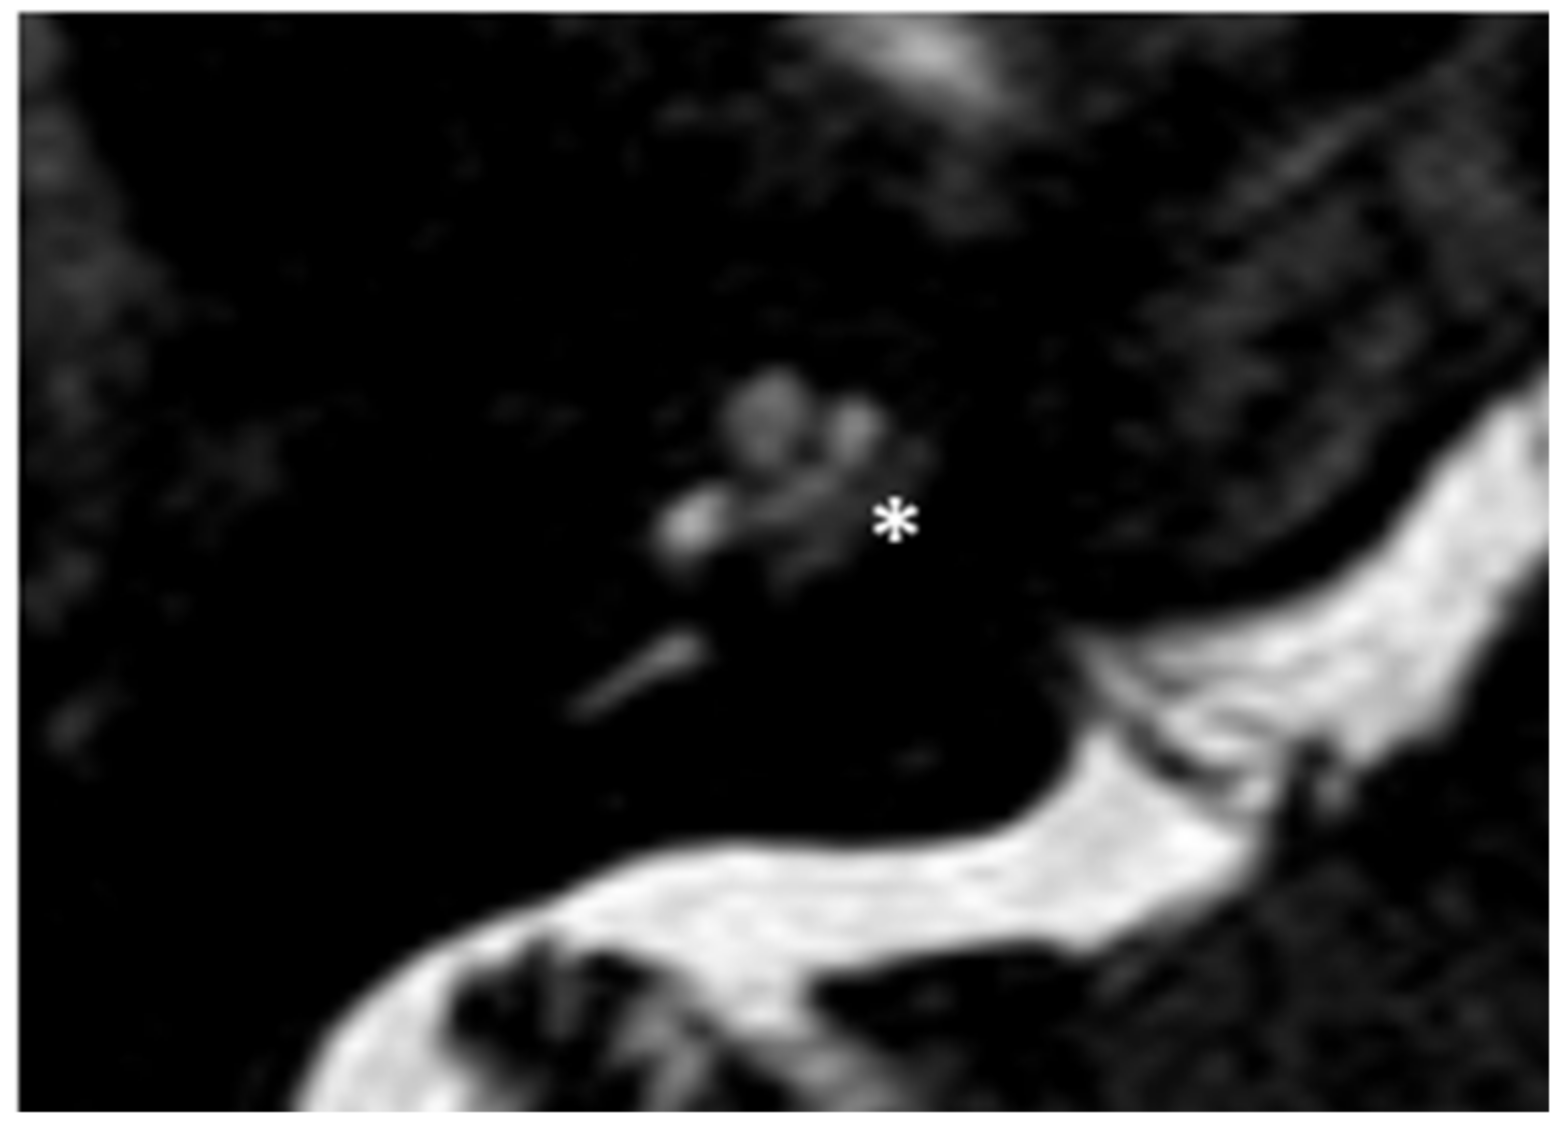

Within a few years, both ears showed a worsening of bone threshold to SNHL bilaterally. In 2017 (27 years since diagnosis) she developed profound SNHL with left-sided anacusis and underwent cochlear implantation in the left ear. CT and MR images showed a large cavity around the basal turn of the cochlea and massive osteorarefaction around the cochlea (‘double ring’ sign). The cavity appeared to contain cerebrospinal fluid but did not communicate with the cochlear lumen (Figure 1 and Figure 2).

Figure 2. MR image of patient #1 with osteogenesis Imperfecta. MR cisternography showing the fluid-signal in the newly formed cavity (white asterisk).